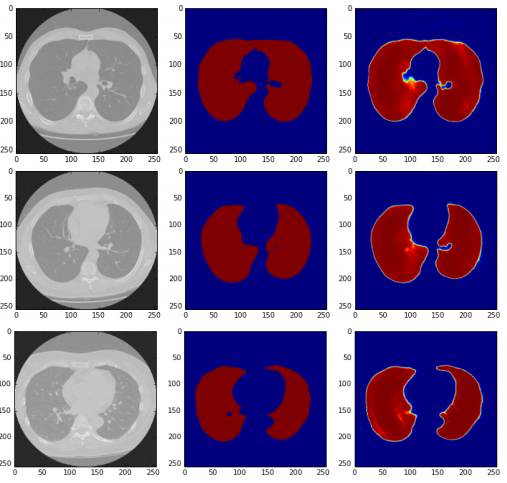

3) 肺分割

2017年在Kaggle Data Science Bowl举办的肺结节分析(LUNA)竞赛旨在通过2D和3D CT图像发现肺部病变。所提供的数据集由534个二维样本组成,这些样本具有用于肺分割的相应标签图像[50]。在这项研究中,70%的图像用于训练,剩下的30%用于测试。原始图像的大小是512×512,但是在这个实现中,我们将图像大小调整到256×256像素。

肺分割是分析肺部相关疾病的重要手段,可应用于肺癌的分割和肺模式的分类,以识别其他问题。本实验采用ADAM优化器,学习速率为2×10-4。我们使用了二进制交叉熵损失,并在训练和验证过程中计算了均方误差。在本案例中,使用了16个batches的150个epoches样本进行验证。表三显示了本文所提出的模型相对于等效的U-Net和ResU-Net模型的表现如何。实验结果表明,在网络参数数目相同的情况下,该模型的性能优于U-Net和ResU-Net模型。